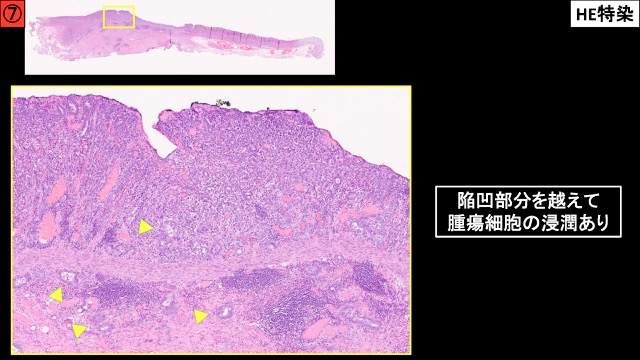

胃002